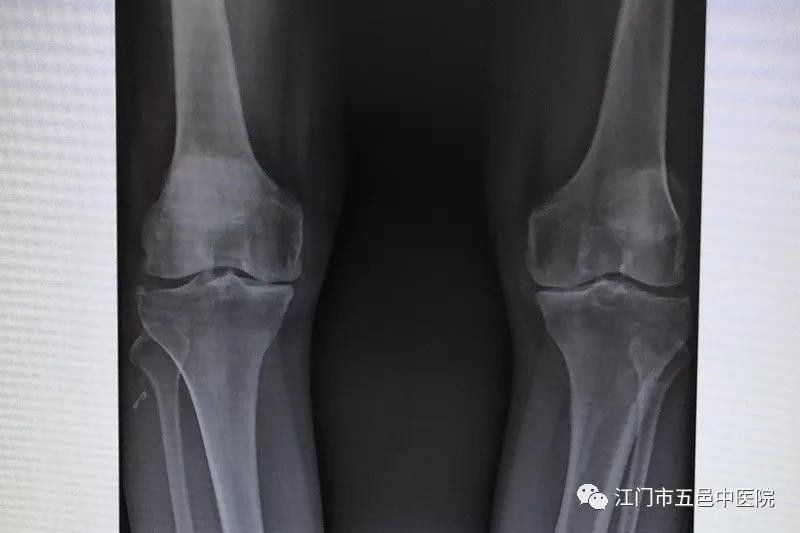

膝关节骨性关节炎根据临床表现及影像可以分为四期:

1期:膝关节爬山或较大活动后症状加重,X线“膝关节无明显异常”。

2期:膝关节肿胀疼痛,急性炎症期屈曲下蹲功能受限,上下楼梯时加重。X线示“内外侧关节间隙不等高,关节缘唇状增生”。

3期:膝关节长期肿胀,屈伸活动明显受限,下蹲后需手撑地或扶物方可站起。X线片可见“内外侧关节间隙明显不等高,关节边缘骨赘形成,软骨下骨硬化”。

4期:常见下肢肌肉萎缩,更显膝关节肿胀、僵硬,伸曲功能丧失,部分人膝外翻或内翻,行走困难。X线片一侧或内外侧关节间隙消失。